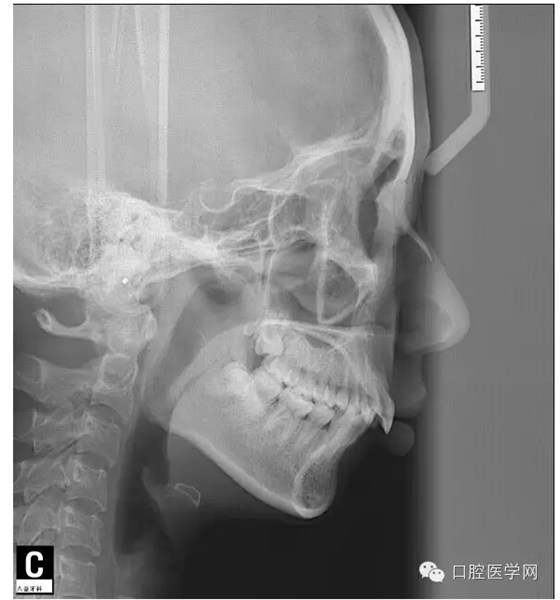

這是一位我同事接診的一位患者,成年女性,安氏II類,高角,下頜后縮,重度深覆合,上下中線右偏,原本做過一次矯正,4個(gè)4已經(jīng)拔除。

這個(gè)患者,II類高角,下頜后縮,所以我們不能抬高磨牙,另外兩個(gè)上頜中切牙牙根短小,也不能大幅壓入。